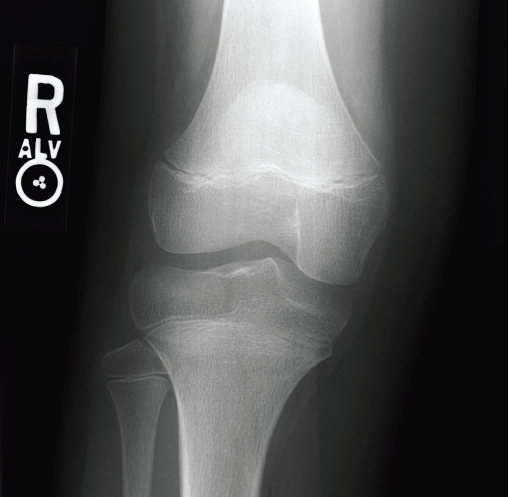

Radiographs obtained in the ED (Figures 1, 2, and 3) helped guide management and diagnosis.

Figure 1. Anteroposterior radiograph of the right knee.